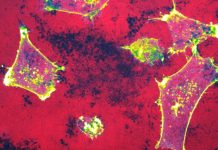

Mesothelioma: Preventable, but no cure

The Government and the public mistakenly seem to think that asbestos is a problem that’s been solved. Despite the UK finally banning asbestos in 1999, it is still very much present in many of our buildings and so the risk of exposure to asbestos is still with us every day. It only takes the inhalation of very low levels of asbestos fibres to be struck down years later with mesothelioma, a cruel cancer that is not survivable.

We do not have a cure for mesothelioma, but it’s a preventable cancer for future generations with the removal of asbestos from all our buildings. The Government’s blunt rejection of the recommendation from the Work and Pensions Select Committee for a dedicated programme for the phased removal of asbestos is numbing.